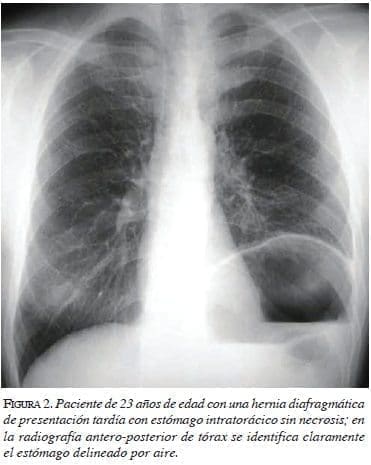

En el hemitórax derecho se puede observar desviación del mediastino hacia ese lado3,4,18-20. El pulmón izquierdo se puede observar colapsado6. Puede identificarse un neumotórax cuando el estómago está perforado14. El hemidiafragma izquierdo se encuentra muy elevado y no se observa la burbuja gástrica por debajo del diafragma3,5,6,20. Ocasionalmente, se puede ver un nivel hidroaéreo en el estómago herniado1,4,5,9,10, el que puede confundirse con un quiste hidatídico o un absceso pulmonar (figura 1). Con mayor frecuencia aún, es posible identificar el estómago dentro del tórax (figura 2). Estas alteraciones se pueden asociar a derrame pleural izquierdo6,18,19. La instalación de una sonda nasogástrica puede demostrar la presencia del estómago dentro del tórax hasta en 95 % de los casos y, además, contribuye a descomprimir el estómago y aliviar la presión intrapleural6,8,10,17.